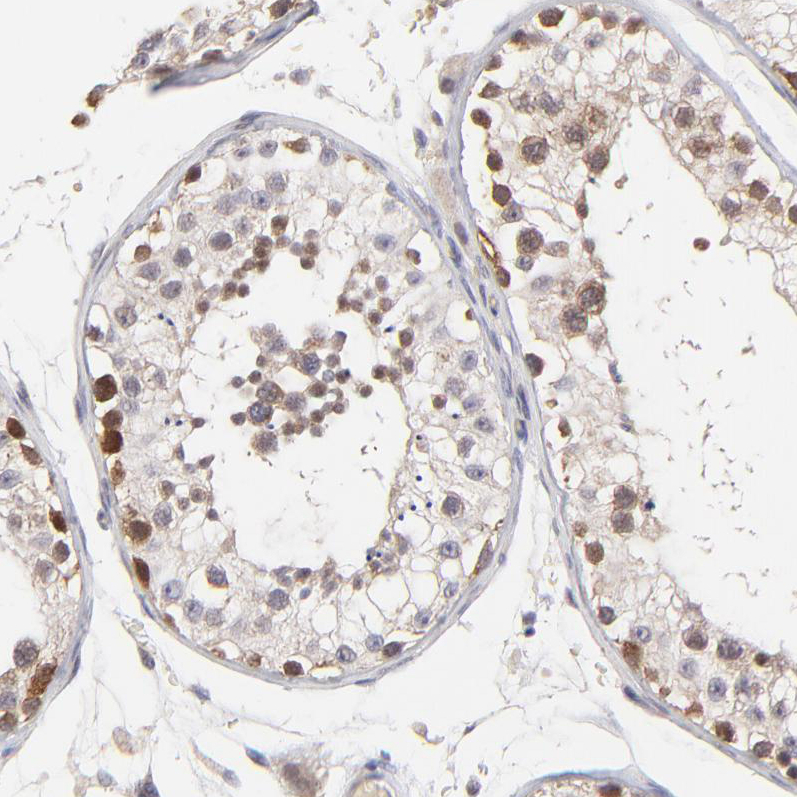

Immunohistochemical staining of human testis shows weak to moderate nuclear and cytoplasmic positivity in a subset of cells in seminiferous ducts.